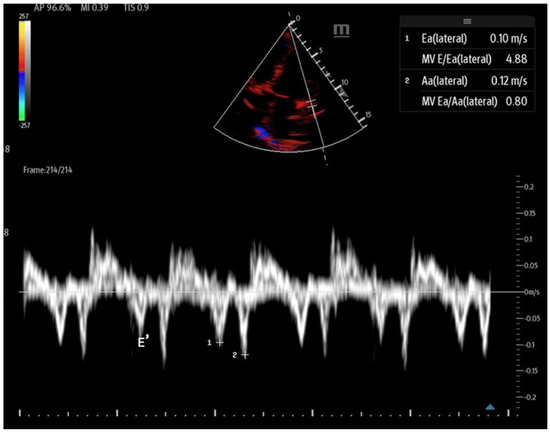

Assessing left ventricular (LV) relaxation offers key insights into left-sided filling pressures, which can guide fluid and diuretic management based on the patient’s volume status. This evaluation also aids in distinguishing between pulmonary edema caused by elevated left atrial pressure (LAP) or primary lung disease. Imaging mitral inflow and myocardial tissue velocities allows the identification of abnormal relaxation patterns, with two commonly used point-of-care ultrasound measurements—mitral inflow and tissue Doppler—demonstrating 90% accuracy in diagnosing diastolic dysfunction in ICU patients [62].

Figure 14. Mitral inflow with PW Doppler gate at mitral valve tip (E and A waves). - Tissue Doppler: Measures myocardial movement during diastole using tissue Doppler at the septal annulus. The E/e′ ratio is calculated from the recorded e′ wave (Figure 15).

Figure 15. Tissue Doppler at the lateral septal annulus to record the E′ wave (labeled).

When abnormal, these values can indicate diastolic dysfunction and its severity (Table 3). However, certain factors, such as mitral annular calcification, basal wall motion abnormalities, mitral stenosis, and significant mitral regurgitation, can affect mitral inflow velocities and invalidate measurements. Additionally, tachycardia may cause the fusion of the E and A waves, and atrial fibrillation can lead to variable RR intervals, further complicating accurate assessment [63]. It is important that while these assessments can be performed with bedside POCUS, accurately interpreting advanced diastolic parameters often exceeds the scope of non-cardiologist operators and may necessitate formal transthoracic echocardiography.